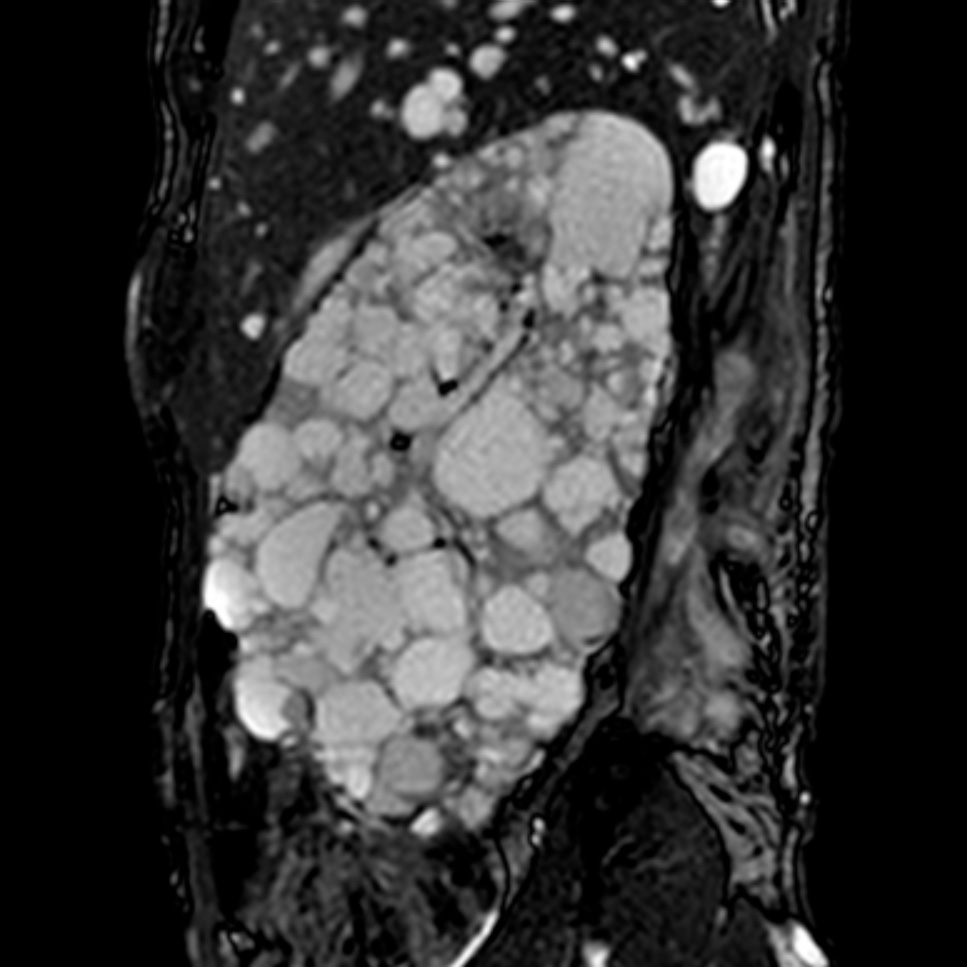

Author: Maria Teresa Sciarrone Alibrandi, Italy

Kidney imaging

Info: Outside-in fistulization in ADPKD: a trivial lumbar skin lesion progressed into a 14-cm deep tract traversing abdominal wall planes to pararenal fascia and psoas, without renal communication. Sterile cultures belied aggressive spread. MRI exposed the full extent, highlighting an unrecognized connective tissue fragility as an important determinant of disease behavior.

From: Maria Teresa Sciarrone Alibrandi, Pierpaolo Bianca, Rodolfo Fernando Rivera, Italy